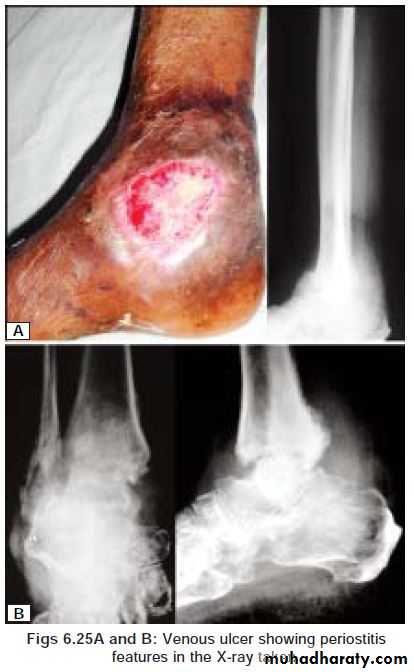

Gaiter area